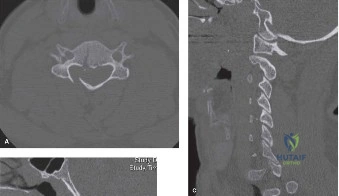

When surgical intervention becomes unavoidable, meticulous pre-operative planning is the cornerstone of a successful outcome. Advanced imaging is non-negotiable. An MRI with and without gadolinium contrast is the gold standard for defining the extent of the epidural abscess, the degree of neural compression, and the involvement of adjacent paraspinal musculature (e.g., psoas abscess). T1-weighted images typically show hypointense signals in the infected marrow, while T2-weighted and STIR sequences reveal hyperintense fluid and edema in the disc space and vertebral bodies. Gadolinium enhancement highlights the vascularized inflammatory phlegmon and the capsule of any abscesses.

In addition to MRI, a fine-cut computed tomography (CT) scan is essential for evaluating bony destruction. CT allows the surgeon to assess bone stock for pedicle screw purchase and to template the size of the interbody cages required for anterior column reconstruction. Upright standing radiographs (if the patient can tolerate them) or full-length supine films are necessary to evaluate global spinal alignment and regional kyphosis.

Once instrumentation is placed, a wide laminectomy is performed at the affected level. The ligamentum flavum is excised, exposing the thecal sac and traversing nerve roots. If an epidural abscess is present, it is meticulously evacuated using gentle suction and blunt dissectors. The nerve roots are then mobilized medially to access the infected disc space via a transforaminal approach.

A radical discectomy is performed. All necrotic disc material, infected cartilaginous endplates, and sequestered bone must be aggressively removed using curettes, pituitary rongeurs, and high-speed burrs until punctate bleeding from healthy cancellous bone is encountered. This aggressive debridement is critical for eradicating the bacterial biofilm and providing a vascularized bed for subsequent fusion. Copious irrigation with sterile saline (often several liters) is employed to mechanically wash out residual bacterial load.